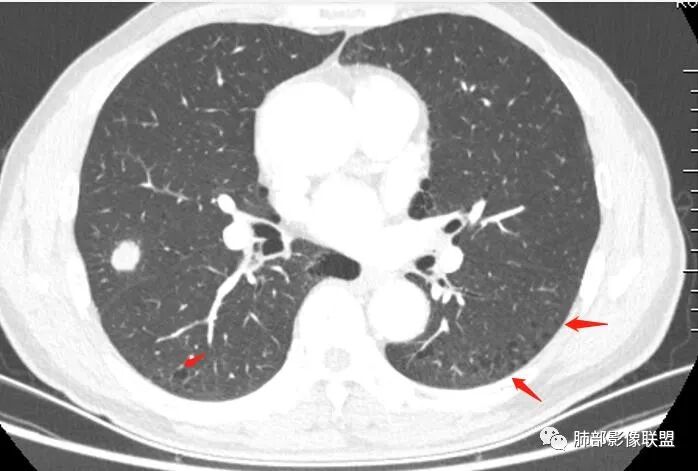

晨读:双肺胸膜下多发小气囊,大小不一,右肺结节,内部可见小空洞,洞壁光滑,厚薄不一,偏心性生长,近段血管束增粗,有分叶,毛刺(软),有晕征,平扫密度尚可,增强后不均匀强化,可见低密度坏死,及部分血管穿行,体检发现,考虑恶性:腺癌,鉴别炎性结节

右上叶结节,轻分叶,结节有长短不一毛刺,结节周围GGO边界清,有血管集束征,肺窗结节周围似可见卫星灶,可见鬼脸征,良恶性征象都有,但GGO边界清,浸润性腺癌耍考虑,临床症状轻微,体捡发现,似可见卫星灶和鬼脸征,炎性肉芽肿TB或隐球菌要鉴别。

虽然良恶性征象都有,但是这个病灶增强后坏死比较明显,如果是恶性:腺癌这样大小的结节坏死很少见,只有低分化腺癌可以坏死,但是低分化腺癌这种大小一般会有周围转移表现(叶间胸膜结节,癌淋或者淋巴结明显肿大),如果是鳞癌,收缩力,坏死情况以及没有支气管截断都不太支持,而且结节远端有几个小结节样改变,大家可能认为是血管,但我觉得应该是卫星灶。所以觉得隐球可能较大。壁胸膜的牵拉线也没有引起胸膜凹陷,比较纤细,至于病理中的丝状物不一定是真菌菌丝。

这个病例确实有很多隐球菌的特点,包括周围的卫星灶、周围的毛刺,它没有粗短的毛刺,它是稍长一点、柔弱一点的。我是觉得这个符合脐凹征,所以我觉得恶性不能排除,结果错了,是炎性。

这个大部分边缘稍微偏平直一点,血管走行非常自然,包括里面的空泡征样的,影子很干净,边界很光滑,都是些炎性特点。